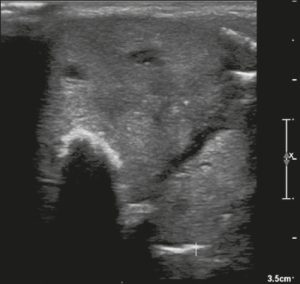

Ở đây, chúng tôi cung cấp các ví dụ minh họa việc áp dụng thực tế hệ thống ACR TI-RADS (Hình 18, 19, 20, 21). Các chú thích dưới hình mô tả chi tiết các mục đã được đánh giá và hiển thị điểm số trong ngoặc đơn.

Hình 18. Hình ảnh nhân giáp dạng đặc (2 điểm), đồng âm (1 điểm), rộng hơn cao (0 điểm), có bờ trơn láng (0 điểm) và không có các ổ tăng âm hay bóng lưng (0 điểm). Do đó, tổng điểm là 3 điểm và mức độ nguy cơ được phân loại là TR3.